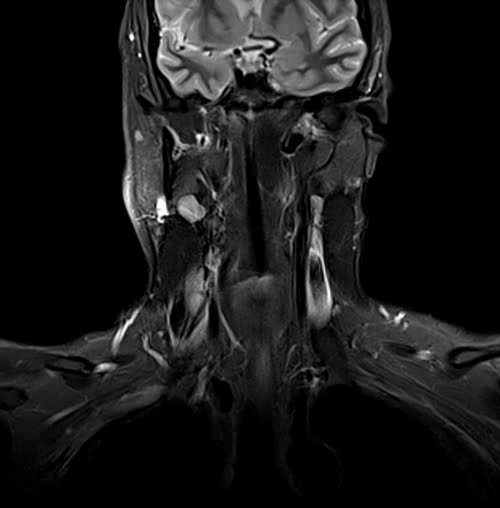

Neck MRI coronal STIR images